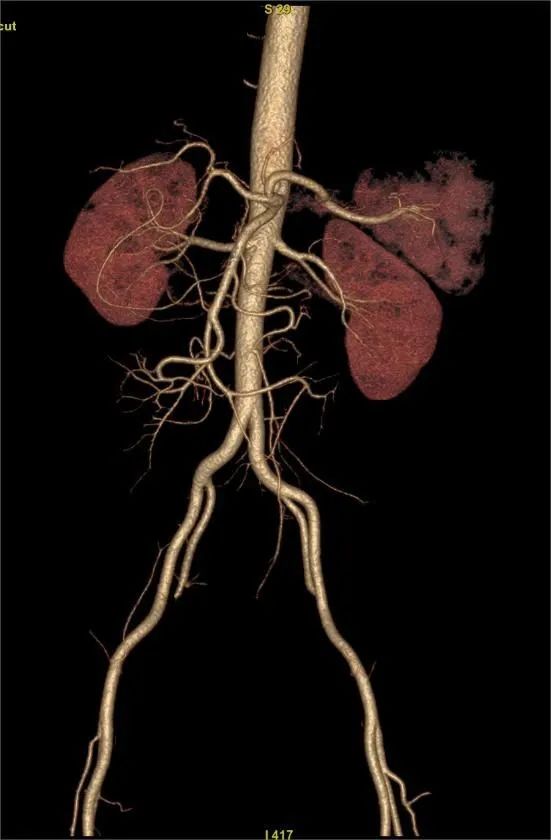

CT小肠造影(CT enterography,CTE)是患者口服或经小肠导管注入对比剂使小肠腔充盈足量对比剂后,经多排螺旋CT增强扫描,并将图像进行后处理,使肠腔、肠壁、肠系膜、腹腔内血管、后腹膜及腹内实质脏器多方位显示出来的技术。临床证明,CT小肠造影(CT enterography,CTE)可精确的判定小肠肿瘤的数目,监测出小肠早期肿瘤,可作为小肠肿瘤定位及诊断的首先检查方法。

CTE简便易行,无明显并发症,不仅能观察肠腔、肠壁、肠外淋巴结、肠系膜、肠系膜血管关系以及毗邻结构等,还可以精确显示粘膜病变、肠壁增厚及肠外并发症,可准确判断小肠肿瘤的浸润深度。适用于多种小肠病变,全腹部扫描能及时发现肿瘤转移情况,有助于临床更准确的把握肿瘤术前分期,能够为患者制定最优治疗方案,带来更好的预后。